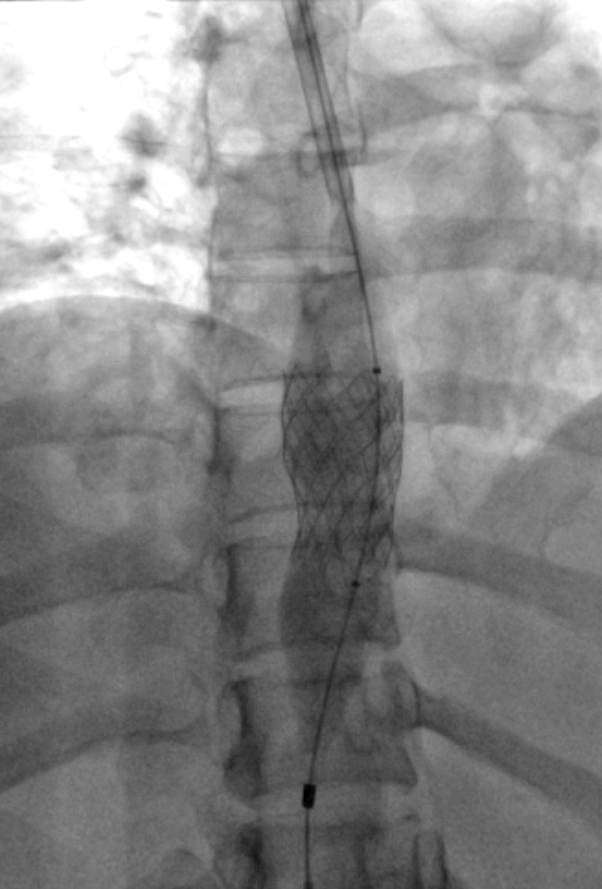

Estenosis vena cava inferior